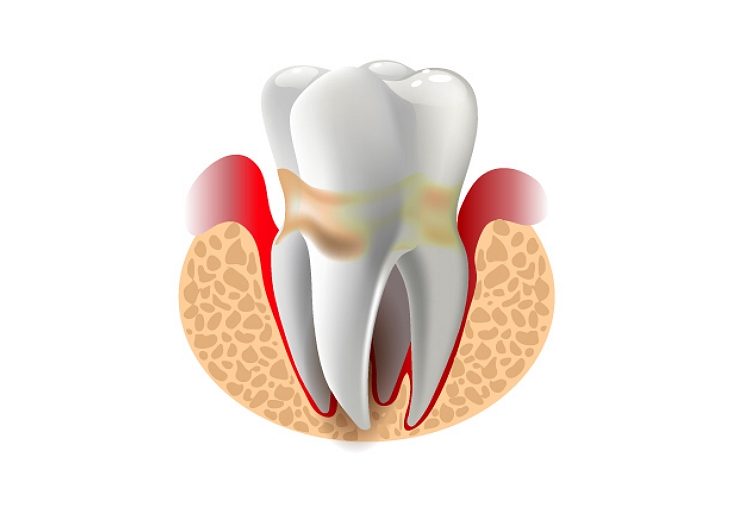

Eine Parodontitiserkrankung schreitet oft langsam und schmerzfrei voran, weswegen sie von den Betroffenen erst spät erkannt wird. Laut aktuellen Gesundheitsstudien sind davon mehr als die Hälfte aller Erwachsenen betroffen. Die Parodontitis kann unabhängig vom Lebensalter auftreten.

Im laufe der Erkrankung verändert sich das Zahnfleisch. Gesundes Zahnfleisch ist hellrosa und fest. Krankes und entzündetes Zahnfleisch ist dagegen rot, meist schmerzempfindlich, blutet leicht und kann auch unangenehm riechen.